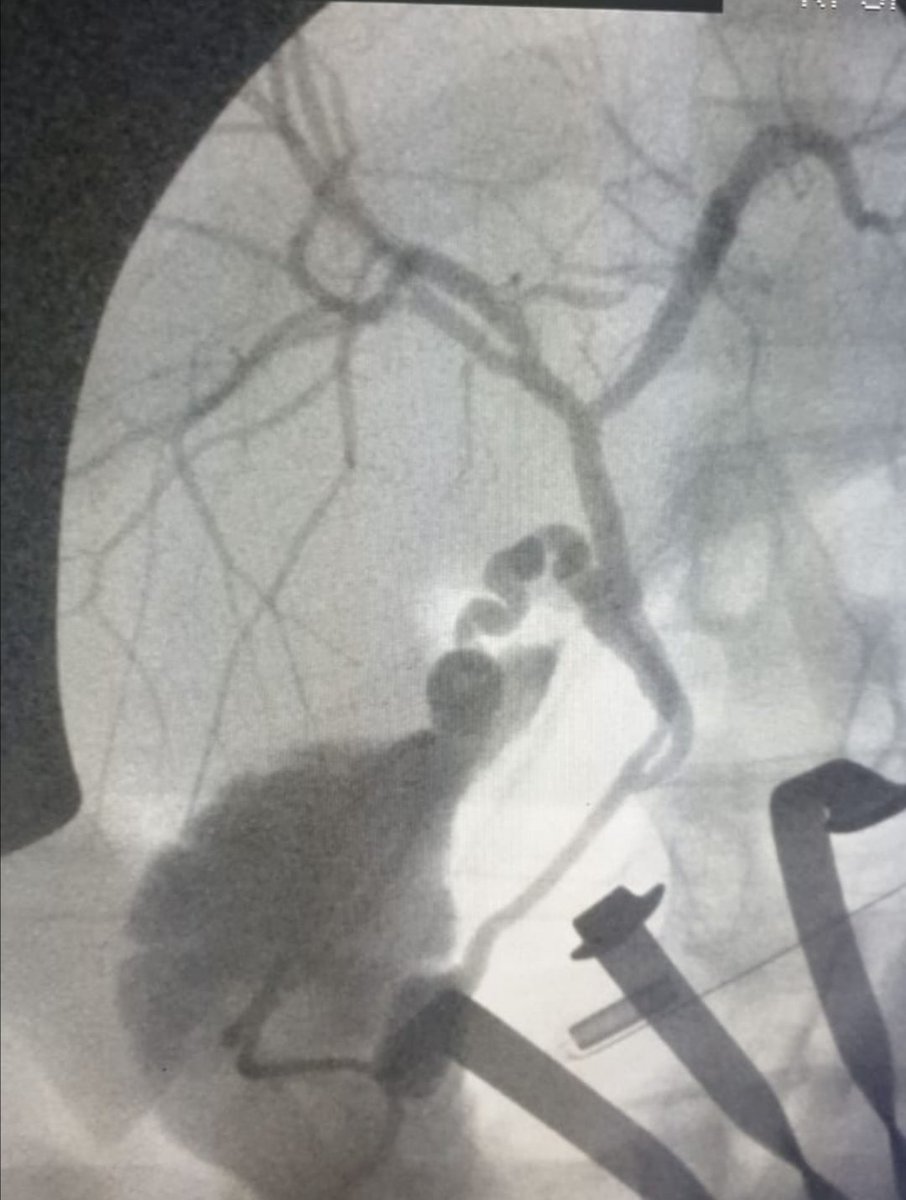

وبعدها نقوم بعمل أشعة بالصبغة للقنوات المرارية